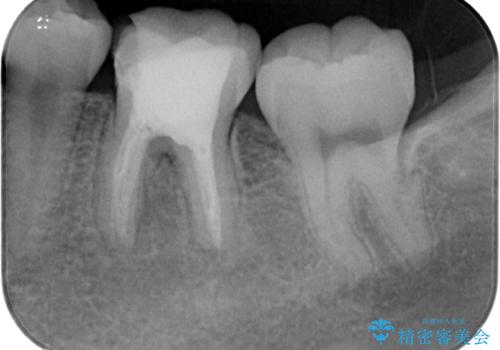

- 神経を取り除いた後に歯の色が変色して気になってきたとのことで来院された患者様です。

前歯は片側のみ神経を取り除かれていましたが、反対側もむし歯治療の詰め物が広範囲に及んでいたため、両方の歯をオールセラミッククラウンにて補綴治療を行うこととしました。

奥歯も著しく茶色に変色していたため、同様にオールセラミッククラウンにて補綴治療を行うこととしました。